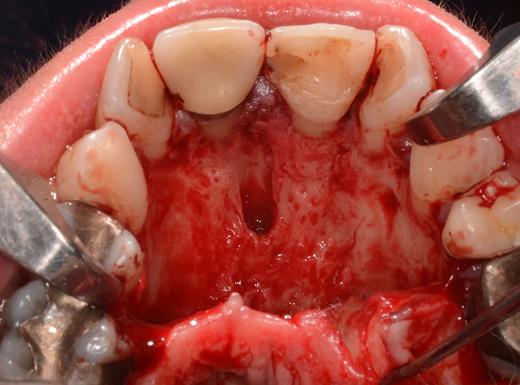

After a sulcular incision on the palatal side from teeth 15 to 25 and an incision in the midline of the palate omitting the incisive papilla and the two orifices of the NPD, two full-thickness mucoperiosteal flaps were raised. Thereafter, the incisive papilla and the whole contents of the incisive canal were enucleated (Figs 4–6). The bony incisive canal was filled with autologous bone harvested from the palatal region (bone scraper) (Fig. 7). A tension-free primary wound closure was achieved by moving the palatal flaps to the midline using single button and interdental vertical mattress sutures (Monocryl 4-0, Ethicon, Johnson & Johnson, USA) (Fig. 8). To avoid wound dehiscence and hematoma, an iodoforme gauze and a palatal plate were applied (Fig. 9). The patient was instructed to rinse three times a day with 0.1% chlorhexidine (formula hospitalis) for 2 weeks postoperatively. Sutures were removed after 14 days.

Situation after removal of the entire soft tissue contents of the incisive canal.